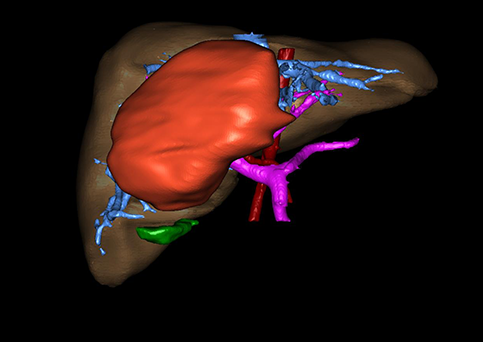

近年来由于数字医学的发展,基于可视化三维重建技术的计算机辅助手术系统极大推进了小儿肝脏肿瘤的精准手术的进步。可以立体透视肝脏解剖、精确掌握肝段的边界、精确测算肝段乃至任意血管所支配的功能体积、准确定位病灶及其与邻近血管的解剖关系,最终对不同手术方案进行比较、筛选和优化。因此,计算机辅助手术规划系统是实现精准肝切除的有力辅助工具,是未来数字外科、精准外科等21世纪外科新理念的重要技术支撑。

计算机辅助手术规划系统具有良好的操作可行性、计算准确性和三维显示效果,可半透明、交互式显示真实的肝内立体解剖关系和空间管道变异,准确计算肝内管道的直径、走行角度,两点间的垂直距离,和任意血管的支配或引流范围等传统二维影像无法获取的信息,有助于实施个体化手术,提高了手术的确定性、预见性和可控性。计算机辅助手术规划系统可直观显示预留肝脏的结构和功能,并可通过虚拟切割功能辅助术者对手术方案进行蹄选和优化,系统评估手术风险和制定对策,改变了部分二维规划的术式和切除范围,使部分二维规划认为不能切除的患者成功手术,提高了手术的根治性、安全性和病变的可切除性,更加符合精准肝脏外科的术前规划要求。详见第11章。

随着计算机技术及影像检查技术的不断发展,以精确的术前影像学和功能评估、精细的手术操作为核心的精准肝切除技术日益受到重视。基于数字医学的计算机辅助手术技术(computer-assisted surgery,CAS)则是实现肝脏精准手术操作的基础。计算机辅助手术系统(CAS)可将术前二维(two dimensional,2D)的CT/MRI影像数据进行三维(three dimensional,3D)重建,建立个体化的肝脏三维解剖模型,清晰显示肝脏内脉管系统的走行及解剖关系,还原病灶与其周围脉管结构的立体解剖构象,准确地对病变进行定位、定性和评估,制定合理、定量的手术方案,实施个体化的肝脏血管取舍分配方案及实施精准肝脏手术。一般认为CAS包括:创建虚拟的患者的图像;患者图像的分析与深度处理;诊断、手术前规划、手术步骤的模拟;术中实时导航。应用本技术后,由于可以更清晰地看出肿瘤的界限,特别是根据肝血管的显影,判断出肿瘤与门静脉及肝静脉的关系以在手术前较准确地估计出手术成功切除的可行性。以往部分根据普通强化CT判断无法手术的病例而被评估为可以成功切除并手术成功。